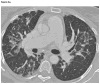

Figures